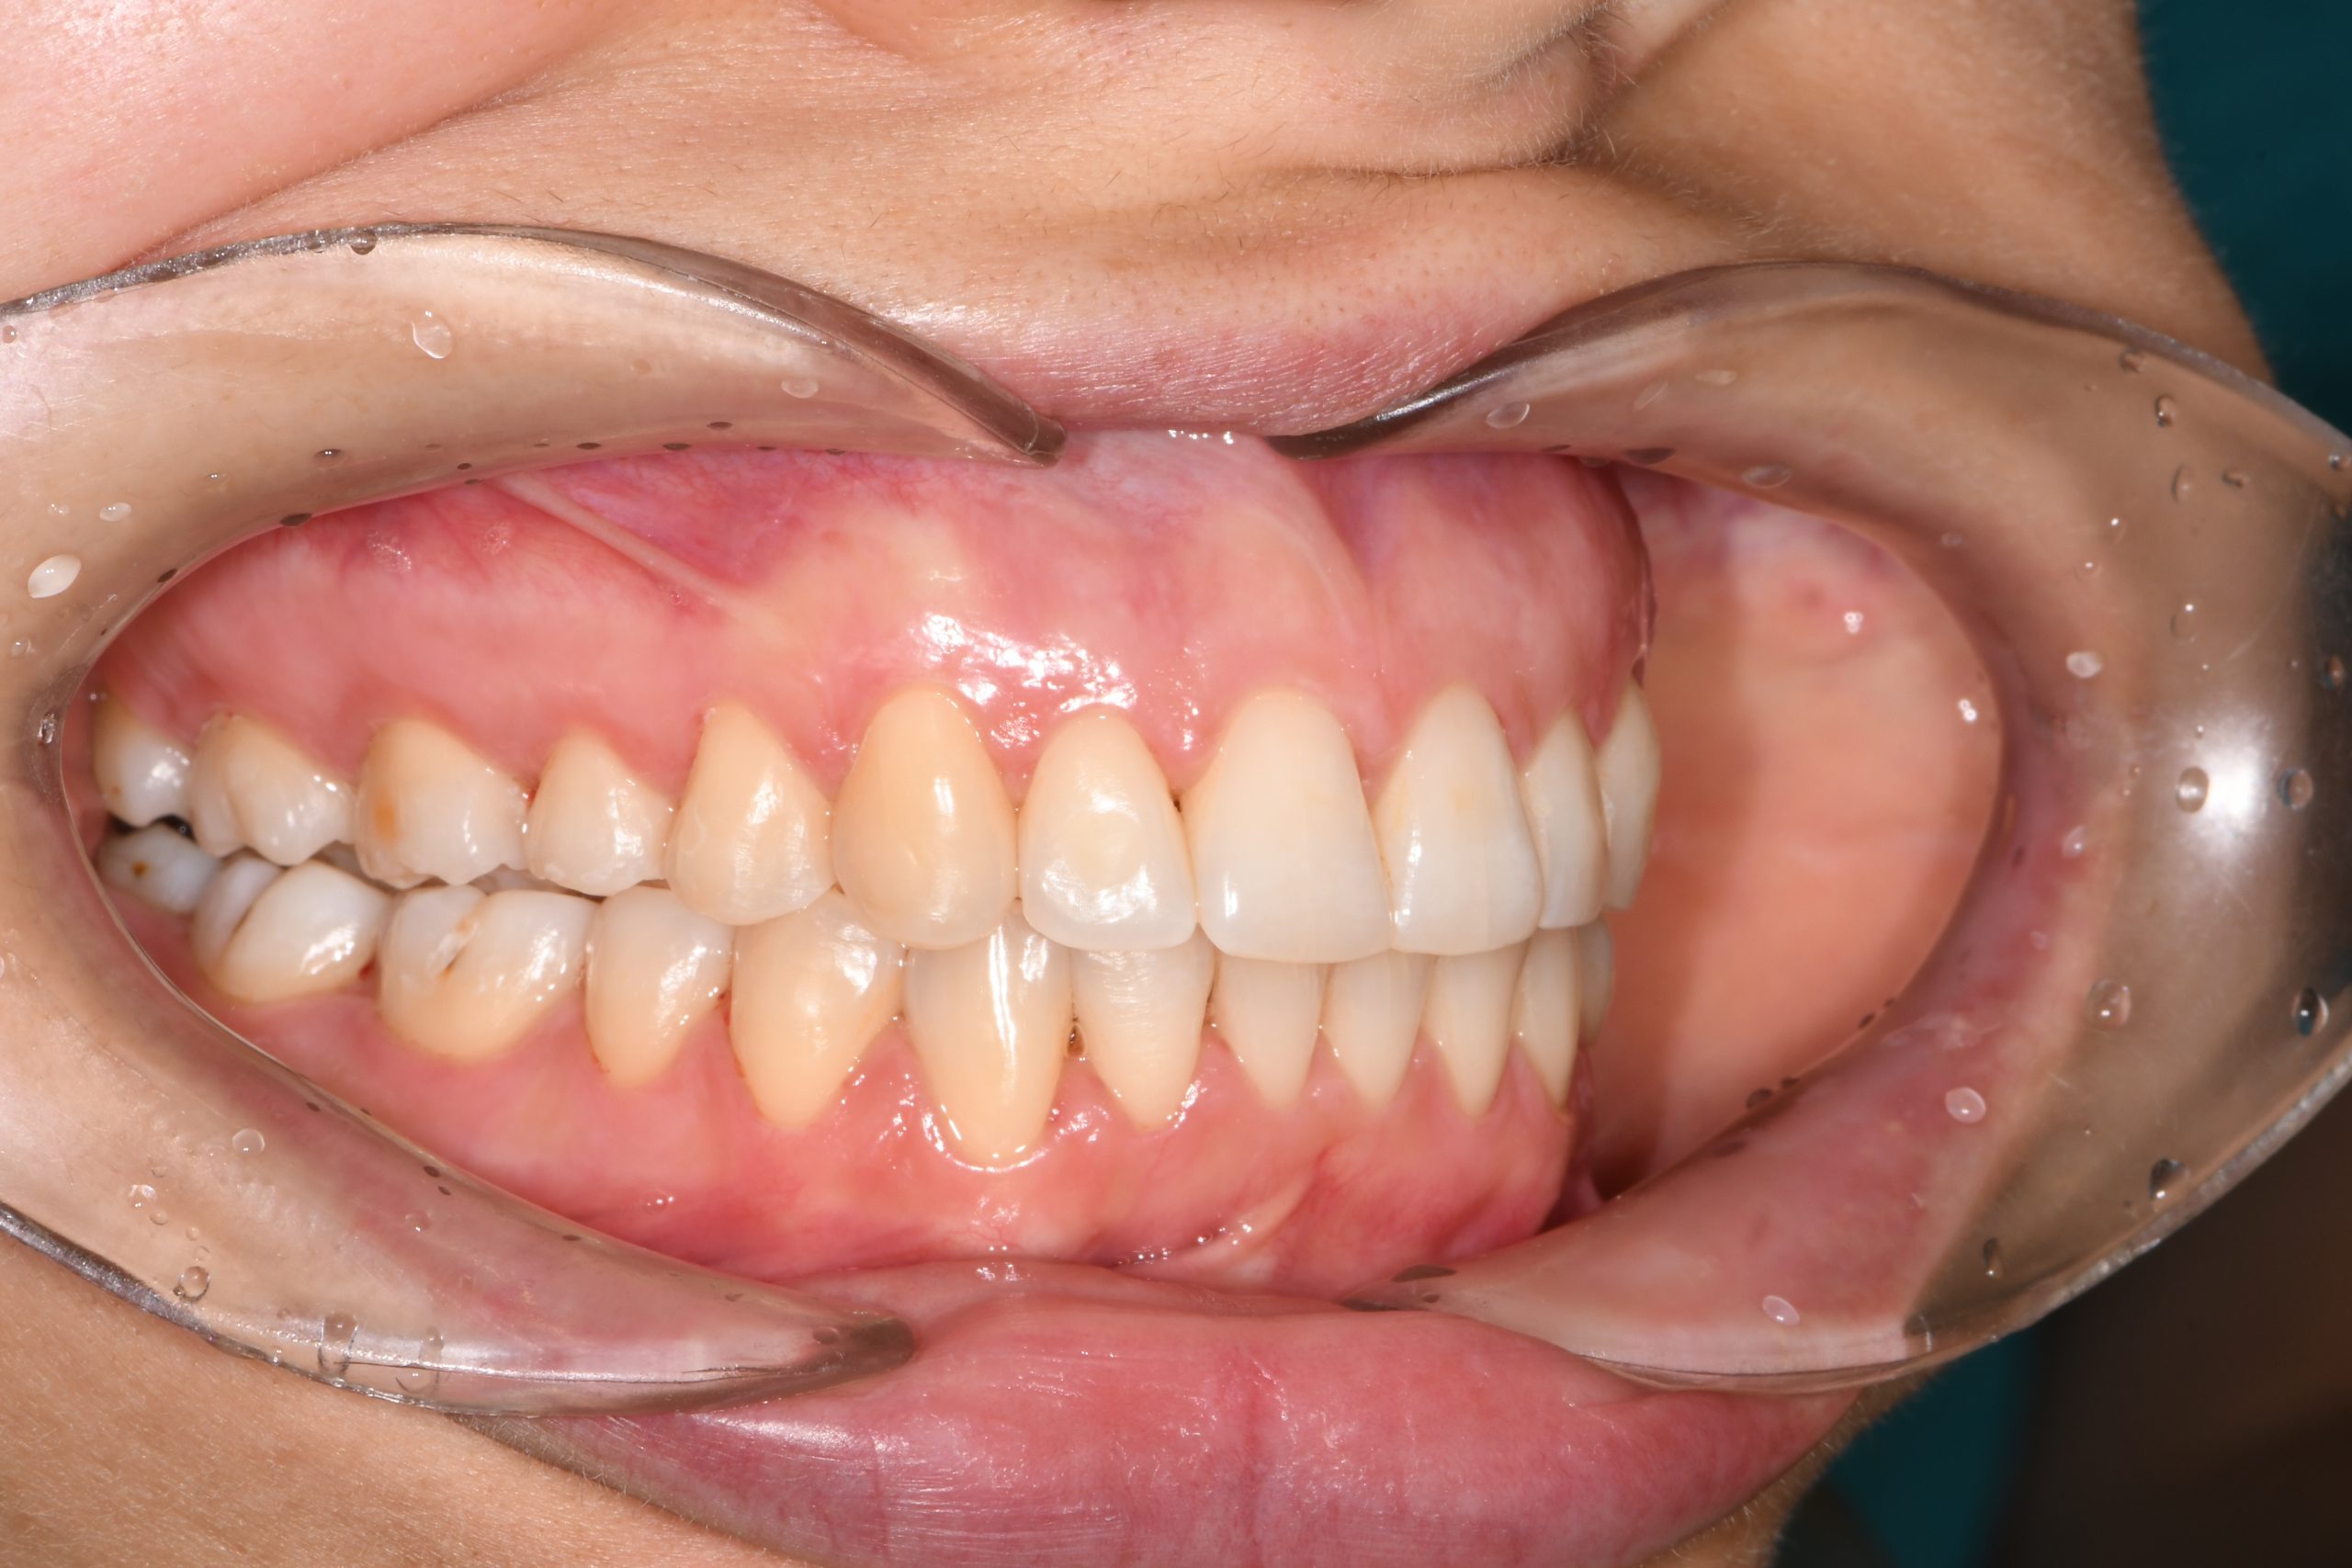

Az elmúlt évekből rengeteg szakmai referenciát tudnánk bemutatni, amelyek különböző fogszabályozási problémákat oldottak meg. Válogatva a több száz esetből, ezen az oldalon olyan képeket, információkat igyekeztünk bemutatni, amelyeknek a segítségével a jövőbeni pácienseinknek azt tudjuk üzenni: A Te fogsorod is lehet gyönyörű!

(Képeket a Pácienseink külön írásos beleegyezésével mutatjuk be!)